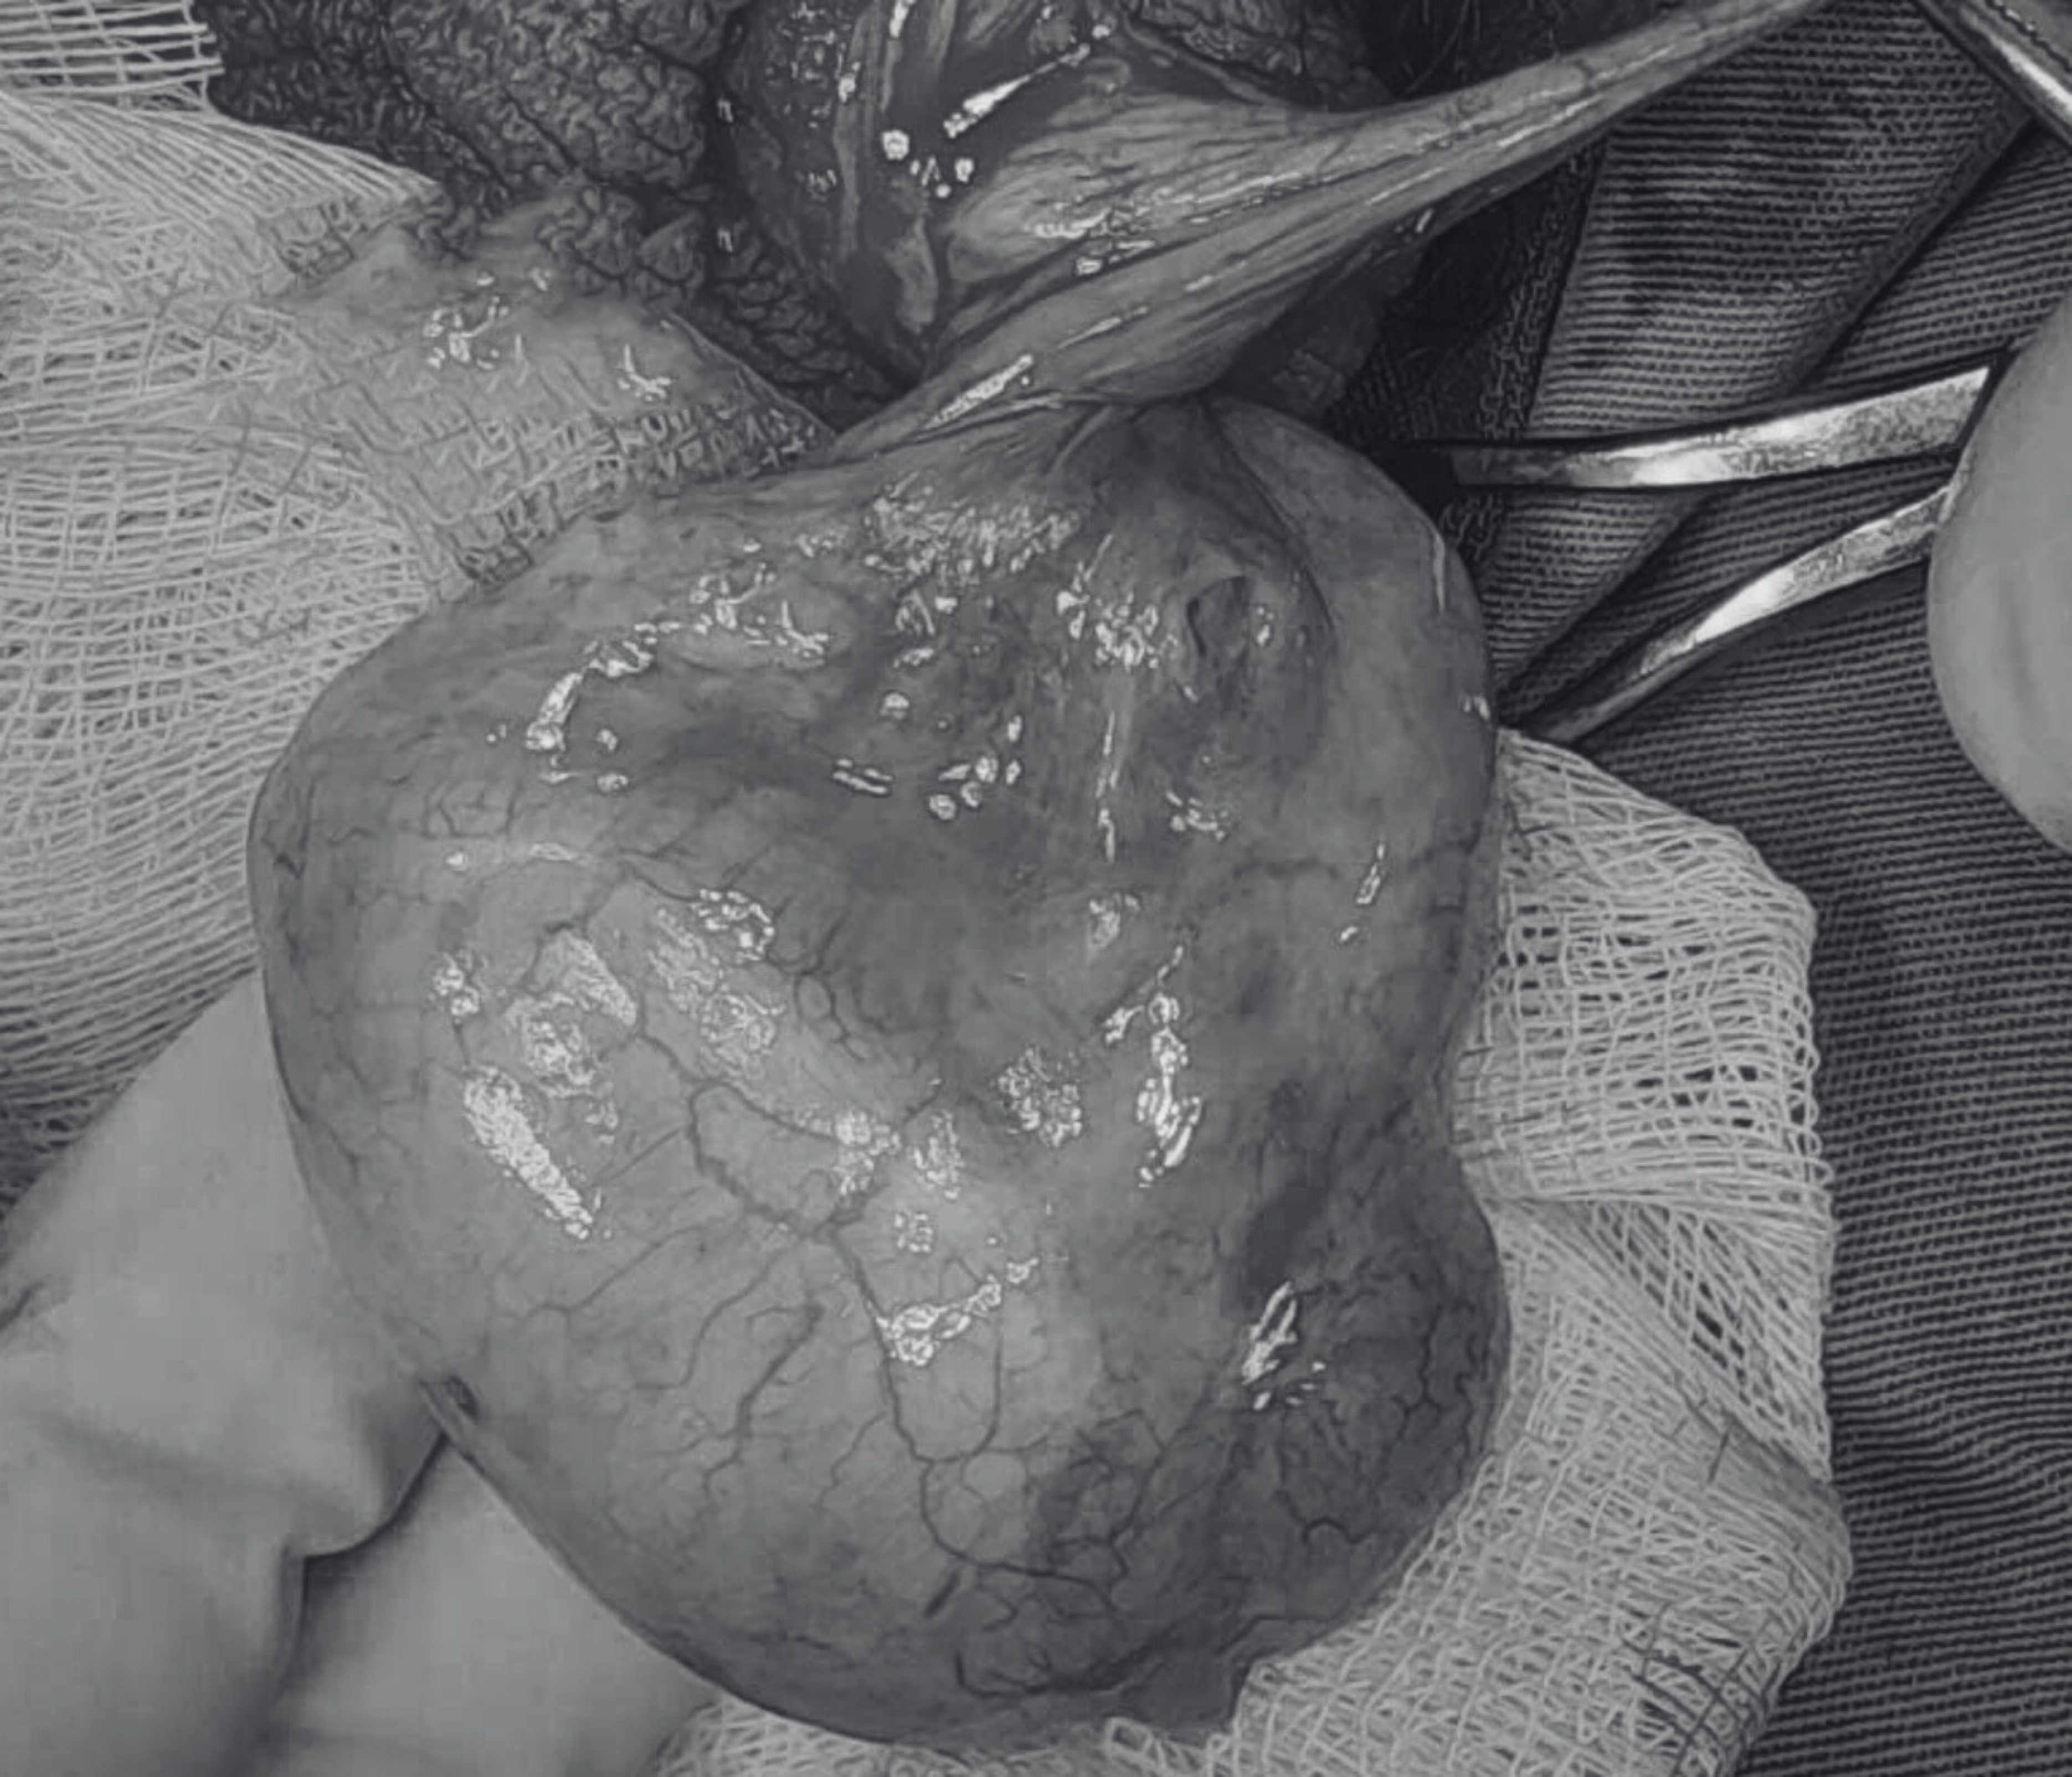

Tại đây, bệnh nhân được khám, siêu âm và được chẩn đoán là xoắn tinh hoàn trái khả năng do chấn thương. Ngay lập tức, bệnh nhân được phẫu thuật cấp cứu, trong lúc phẫu thuật, ban đầu tinh hoàn trái có màu tím (biểu hiện thiếu máu nuôi dưỡng), phù nề và đặc biệt là phát hiện xoắn ở phần mào tinh hoàn. Tinh hoàn được tháo xoắn, chườm ấm, sau vài phút thì hồng hào trở lại. Sau phẫu thuật, bệnh nhân hết đau, sức khỏe ổn định và được xuất viện 3 ngày sau đó.

Hình ảnh xoắn tinh hoàn với bìu trái sưng to do va chạm đá banh.